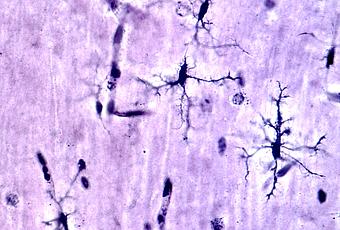

Grâce à une technique d’imagerie de pointe, l’équipe menée par Ukpong B. Eyo (Visuel ci-dessous) chercheur au département des neurosciences de l'UVA et au Center for Brain Immunology and Glia (BIG), constate, pour la première fois que les cellules immunitaires appelées microglies ne font pas qu’éliminer les cellules lésées par les crises mais semblent en réalité « guérir » les neurones endommagés. « De récentes études soutiennent l'idée que la microglie pourrait être utilisée pour réduire les crises, mais jusqu’à cette étude nous manquions de preuves directes et visuelles de leur possible contribution » commente Ukpong B. Eyo.

Exploiter cette fonction possible et naturelle de la microglie pourrait constituer une nouvelle approche thérapeutique prometteuse dans l’épilepsie : ici, les chercheurs observent, chez la souris modèle de crises, que plutôt que de simplement nettoyer les débris cellulaires, la microglie commence à former des poches qui n’engloutissent pas le matériel endommagé, comme le font de nombreuses cellules immunitaires mais « regonflent » les dendrites, les branches des cellules nerveuses qui transmettent l'influx nerveux. En résumé, écrivent les scientifiques, la microglie semble favoriser leur guérison.

Ces petits sacs à processus microglial perdurent pendant des heures, rétrécissent de temps à autre, et semblent redonner aux dendrites une structure et une fonction normales.